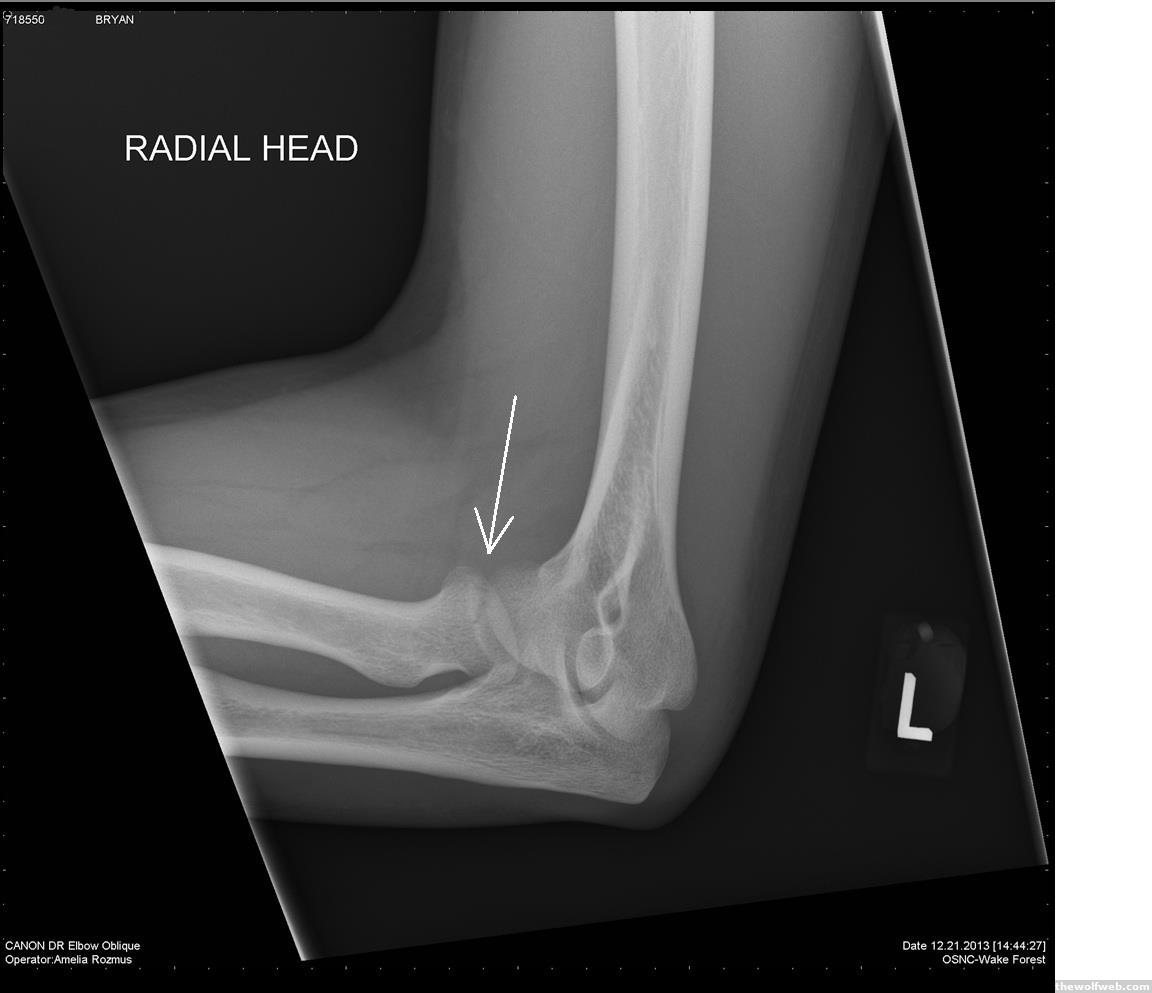

29 yrs going HAM and just now broke my elbow. just goes to show, kids; keep at it and you'll evenyually succeed. this is typed with one hand. so sue me. grammar nazzi, etc-al

Which bone did you break?

By the way, my new band name is "Radial Head". Working on our first single 2+2=4 soon. haha